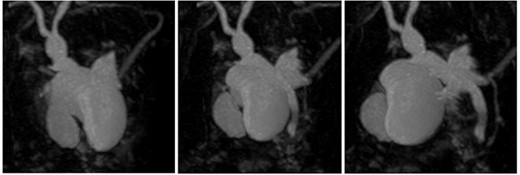

Preoperative T2-weighted MRCP; double cystic ducts seen upon retrospective review of images post cholecystectomy.

3D reconstruction of duplicated gallbladder and biliary tree from MRCP.